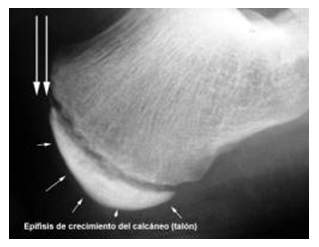

Antes de indicar el tratamiento se debe pedir una radiografía para confirmar el diagnóstico y descartar otras patologías del calcáneo. El tratamiento es sintomático. Mientras ocurre este proceso, se recomiendan llevar las siguientes medidas: